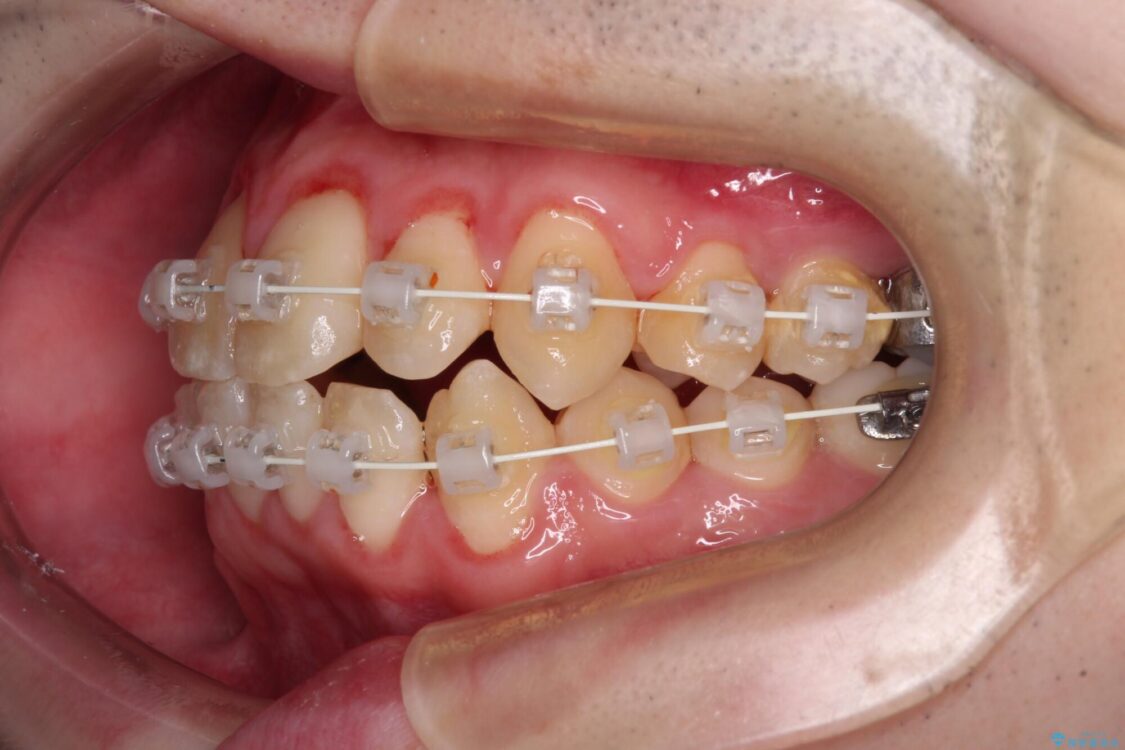

シザーズバイト改善のために補助装置を使用しながら、ワイヤー装置にて全体の歯列を整えることとしました。

治療途中

• 全顎的なクロスバイト 補助装置を用いてワイヤー矯正 治療途中画像

矯正装置

審美装置